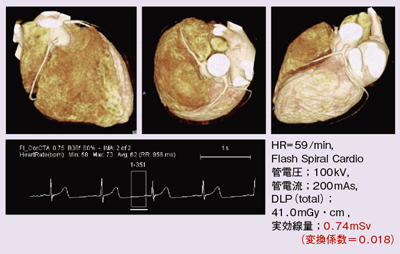

CT装置|徳島赤十字病院, 320列面検出器CTによる新しい冠動脈CT技術 吉岡邦浩(岩手医科,

320列面検出器CTによる新しい冠動脈CT技術 吉岡邦浩(岩手医科, 桜橋渡辺未来医療病院 MDCT検査予約,